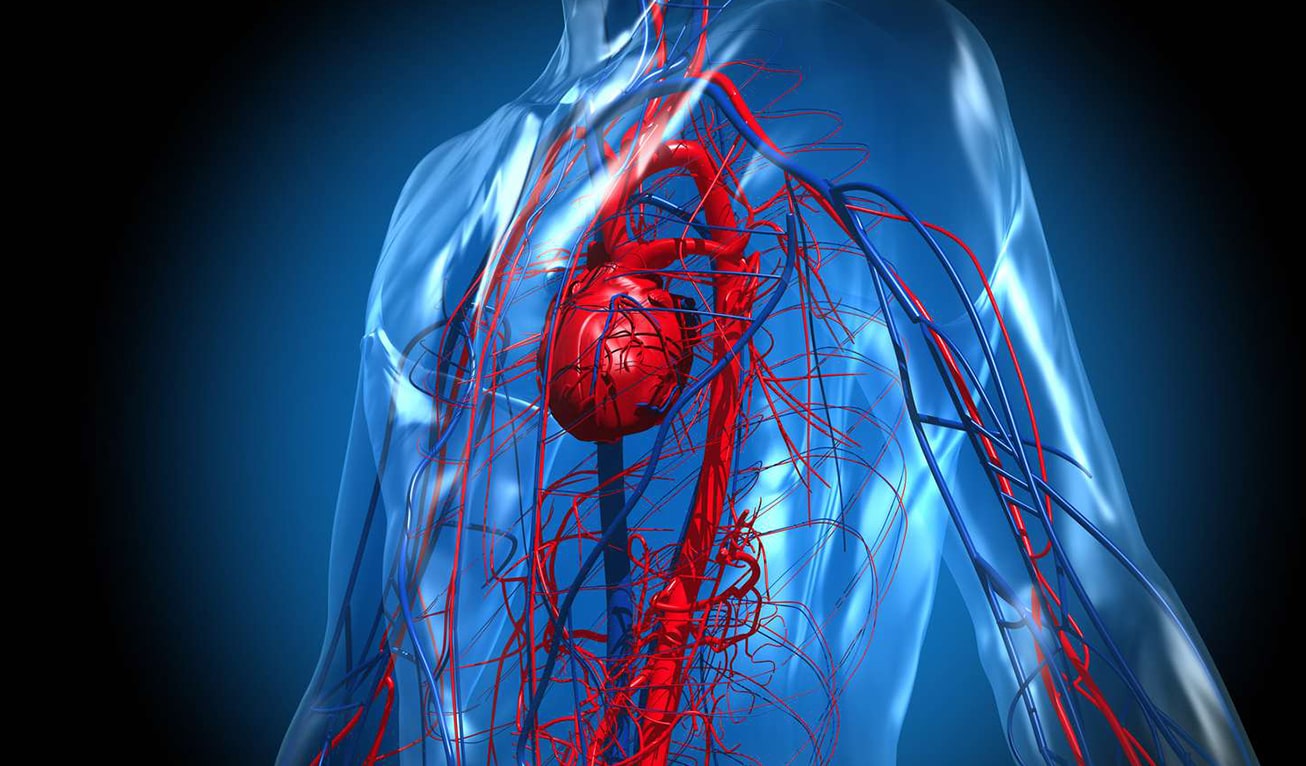

Your heart is the centre of your cardiovascular system, and its health is crucial for overall well-being. It works tirelessly to pump blood and oxygen to all parts of your body, providing essential nutrients while removing toxins and waste. Taking care of your heart is not only about preventing heart disease, but it also plays a significant role in maintaining a healthy heart and leading a fulfilling life.

Heart health goes beyond just the absence of heart disease. It encompasses the overall well-being of your heart and cardiovascular system. Maintaining a healthy heart is essential for several reasons:

A healthy heart allows you to lead an active and fulfilling life. It provides the energy and stamina needed for daily activities, such as work, exercise, and leisure activities. A strong heart also supports a healthy brain, as it supplies oxygen and nutrients to the brain, promoting cognitive function and reducing the risk of cognitive decline.